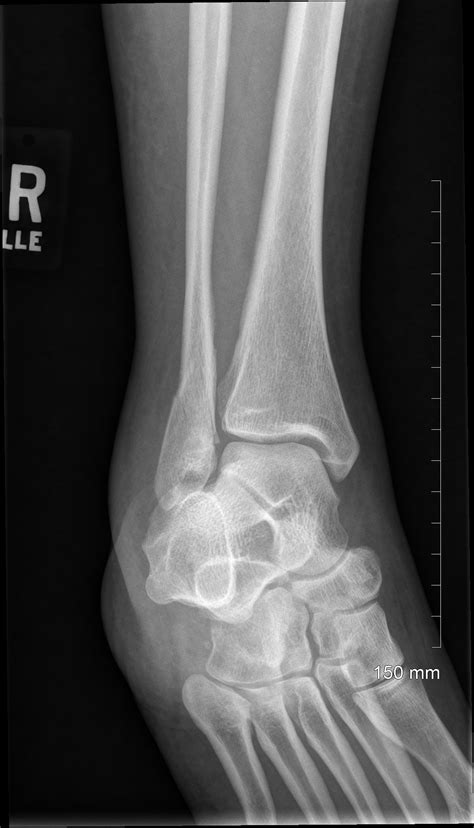

When you visit an urgent care clinic or an emergency room with ankle pain, the physician will first perform a physical examination. However, even the most experienced doctor cannot confirm a fracture just by looking at the surface. A broken ankle Xray is necessary to visualize the internal structure of the joint. It provides a clear, two-dimensional image of the tibia, fibula, and talus, allowing medical professionals to rule out or confirm a break.

By securing an image, the radiologist or orthopedist can identify the exact location and pattern of the break. This accuracy is vital because different types of fractures require vastly different treatments, ranging from simple immobilization in a walking boot to surgical intervention with plates and screws.

Once the images are captured, they are reviewed by a radiologist. The broken ankle Xray will reveal whether there is a cortical breach—the medical term for a break in the bone's outer shell. The report will describe the type of fracture, which helps the orthopedic surgeon plan the treatment.